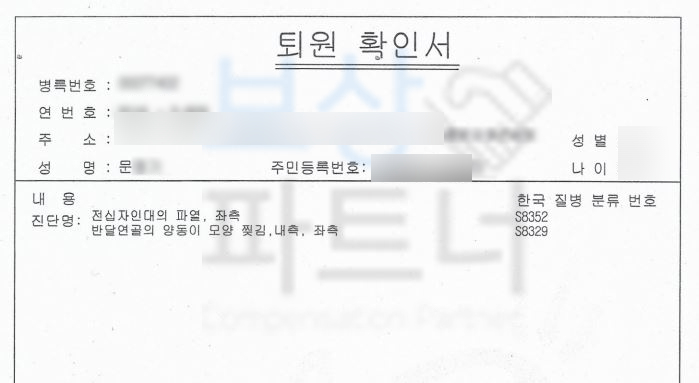

전방십자인대 파열 좌측 s8352

십자인대 재건술을 받으셔야 했죠. 십자인대 재건술을 받았음에도 거동 시에무릎이 흔들거리거나 다리가 툭툭 떨어지는 느낌이 있다면 후유증 보상 즉 후유장해보상 알아보세요.

의뢰인의 보험 증권을 분석한 후 보상의 가능성을 확인하게 되었고 저희는 후유장해보험금 청구를 위임받게 되었습니다.

이후 올바르면서 분명한 장해 진단을 위해 공신력 있는 제3병원의 전문의에게 후유 장해 진단을 받았고!

무릎 관절의 약간의 장해 5%